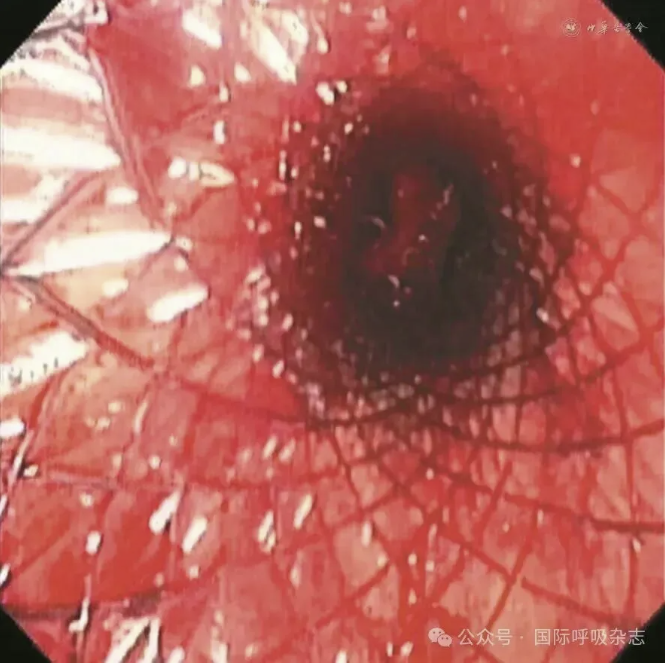

患者男,61岁,因“食管癌术后3年,咳嗽、气喘半年”于2025年3月14日入院。患者于2022年确诊食管鳞癌,曾接受新辅助免疫联合化疗、食管癌根治术、术后辅助免疫治疗、局部放疗及多线化疗等规范治疗。2024年12月经胃镜检查确诊为“气管食管瘘”,遂行空肠营养管置入术(图1)。后因咳嗽、气喘症状持续,辗转多家医院治疗效果不佳就诊于西安市胸科医院。入院查体:端坐呼吸,声音嘶哑,双肺可闻及湿性啰音及喘鸣音。实验室检查示炎症指标升高:白细胞计数8.82×109/L,中性粒细胞比例88.8%,C反应蛋白165.88 mg/L。血气分析pH值7.435,PaCO2为45.2 mmHg(1 mmHg=0.133 kPa),PaO2为55 mmHg,氧合指数200 mmHg,提示Ⅰ型呼吸衰竭。胸部CT提示气管食管瘘,伴双下肺感染及实变(图2)。支气管镜下见气管中下段膜部菜花样新生物,新生物下方可见瘘口(图3)。

图3:61岁男性气管食管瘘患者支气管镜检查(2025年3月15日)示气管中下段膜部可见菜花样新生物,于新生物下方可见气泡冒出,考虑瘘口形成